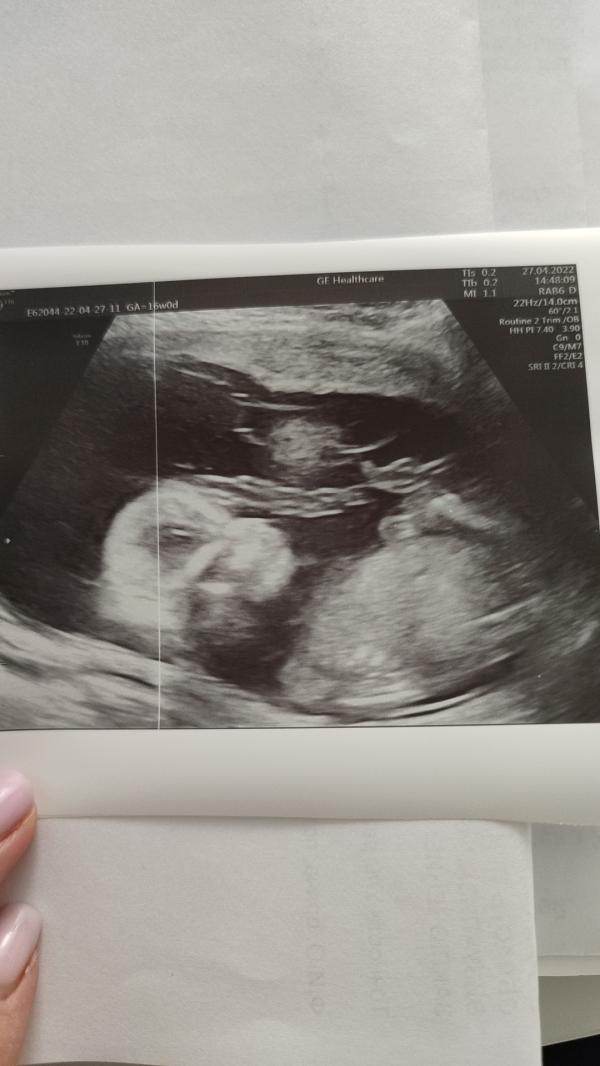

Сходила на УЗИ по определению пола. Счастью нет предела, после двух сыновей будет доченька😍

Сначала была у Газизовой, она точно не сказала, но предположила. Потом сходила только на определение пола в добрый Доктор к Митрофанову

@marichka1012 я боялась только двойни в третий раз 😁 и почему-то до последнего были уверены, что опять мальчик будет, на 1 УЗИ не поверили даже, сейчас уже третье прошли - все разы девочку подтвердили)